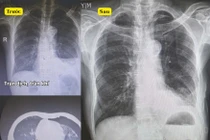

Từ khóa: xử trí cấp cứu tràn khí màng phổi